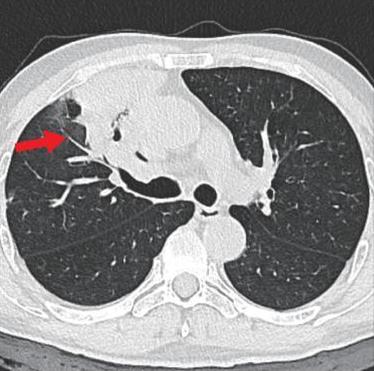

• 侵袭性肺真菌病的支气管镜表现及介入治疗效果

2025, 31(9):81-90. DOI: 10.12235/E20250317

摘要 (112) HTML (56) PDF 6.06 M (77) 评论 (0) 收藏

摘要:目的 探讨侵袭性肺真菌病(IPFD)的支气管镜表现,并评估介入治疗的安全性和疗效。方法 回顾性分析2018年5月12日-2025年5月12日于该院行支气管镜检查的35例IPFD患者的临床资料,观察IPFD的支气管镜表现及介入治疗效果。结果 共收集35例患者临床资料。其中,男22例,女13例,患者年龄(53±14)岁。基础疾病包括:血液系统恶性肿瘤10例,长期应用糖皮质激素者5例,2型糖尿病者4例,肺部恶性肿瘤2例,器官移植1例。胸部CT显示:肺部病变累及单肺叶者19例,累及多肺叶者16例。支气管镜下表现主要为:黏膜充血水肿29例(82.9%)、坏死物堵塞管腔22例(62.9%)、大量黏稠脓性分泌物17例(48.6%)、支气管部分狭窄或闭塞16例(45.7%)、黏膜坏死9例(25.7%)、黏膜出血5例(14.3%)、真菌球3例(8.6%)。其中,32例(91.4%)接受全身性抗真菌治疗,17例(48.6%)接受支气管镜局部两性霉素B灌注治疗,10例(28.6%)采用活检钳钳除病灶,6例(17.1%)采用冷冻探头冻取病灶,4例(11.4%)接受氩气刀治疗。28例(80.0%)临床症状明显改善,肺部影像学病灶缩小或消退;4例(11.4%)病灶稳定;3例(8.6%)未完成治疗。结论 IPFD多见于免疫抑制宿主,支气管镜常表现为:坏死物堵塞管腔、伴脓性分泌物、支气管管腔狭窄和局部黏膜充血水肿或坏死。全身抗真菌药物联合支气管镜下介入治疗,安全性高,且疗效好。